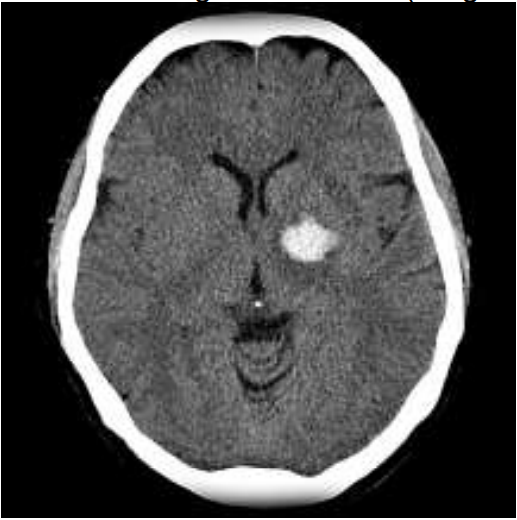

Mulher de 54 anos, tabagista, com diagnóstico de hipertensão e diabetes prévio, cursou de forma súbita com hemiparesia proporcionada completa à direita. Procurou serviço de emergência, vigil, consciente, disártrica, desorientada em tempo e orientada em espaço, obedecendo comandos, sensibilidade, coordenação sem alterações, NIHSS 10. Após 1h30 do ictus realizou tomografia de crânio (imagem).

Tomografia de crânio com volume estimado do hematoma menor que 30ml